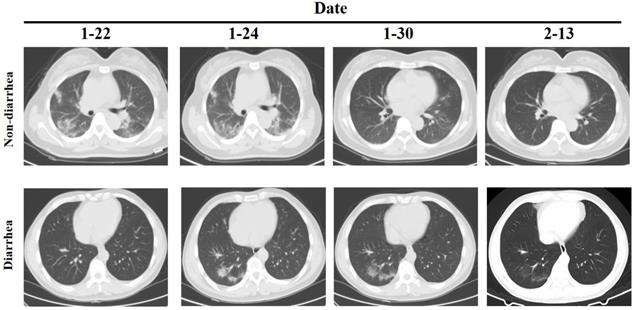

However, the clinical examination of patients with diarrhea as the main symptom is not clear. We further analyzed the differences between 8 diarrhea patients and 62 non-diarrhea patients. The Eight patients had diarrhea as the first symptom, and the throat swab test was negative but the anal swab test was positive, and except for one patient who had slight inflammation of the lungs when admitted, the other patients had no obvious inflammatory changes in the lungs (Figure 1). There was no significant difference between the two groups in the general situation of age, gender, medical history, etc. (Table 3). Comparison of clinical test indicators between the two groups of patients found that GGT (diarrhea vs. non-diarrhea: 20.75±14.12 vs. 54.74±59.61; P=0.000) was significantly different. The results indicate that GGT may be a deliberate detection index for patients with diarrhea. Further analysis of clinical test indicators of 8 patients showed that the Lymphocyte (4/8), PLT(2/8), CRP (4/8), PT (2/8), Prealbumin (5/8), Creatinine (2/8), Cystatin C (4/8), C4 (3/8) and CD8 (3/8) had significant differences (P<0.05). Among these indicators, only Lymphocyte, CRP, Prealbumin and Cystatin C positive rate is more than 50%. Although there is no statistical difference in GGT, 100% of the 7 patients tested decreased, so it further illustrates the important detection value of GGT in patients with diarrhea.

Figure 1

CT of chest in patients with diarrhea and non-diarrhea.